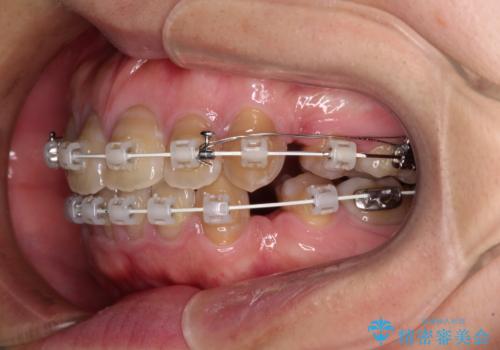

- 審美装置

上下前歯が著しく前突している状態であったので、上下左右の第1小臼歯4本を抜歯し、ワイヤー装置にて矯正治療を行うこととしました。

4本の歯を抜歯したことで、飛び出していた口元が引っ込み、横顔が大きく改善されました。